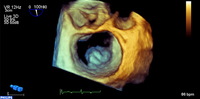

Regurgitação mitral

Prolapso do folheto P2 da valva mitral: visualização 3D

Do acervo de Prakash P. Punjabi